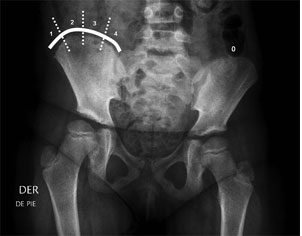

Está destinado a aquellos pacientes que están fuera del alcance ortopédico. Es decir pacientes con curvas sobre 45º, rígidas, mayores de 14 años, Risser 4, o que las curvas hayan aumentado dentro del corsé. El índice de Risser para estimación de maduración ósea, evalúa el grado de aparición del núcleo de osificación de la cresta ilíaca y su fusión al ala ilíaca, como se observa en la tabla. El grado de madurez ósea es otro de los factores pronósticos de la escoliosis idiopática, existiendo una mayor progresión de la curva en niños con un grado de Risser 0 ó 1, que en grados 2 a 5. La ventaja de utilizar este método es que las alas ilíacas están frecuentemente incluidas en la radiografía, por lo que sería innecesario contar con radiografías adicionales para la estimación de edad ósea(4). Indice de Risser